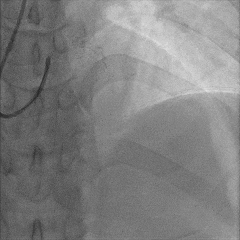

冠脉造影:

冠脉功能学全面评估:

▶IMR:80(+);CFR:1.0(+);FFR:0.82。